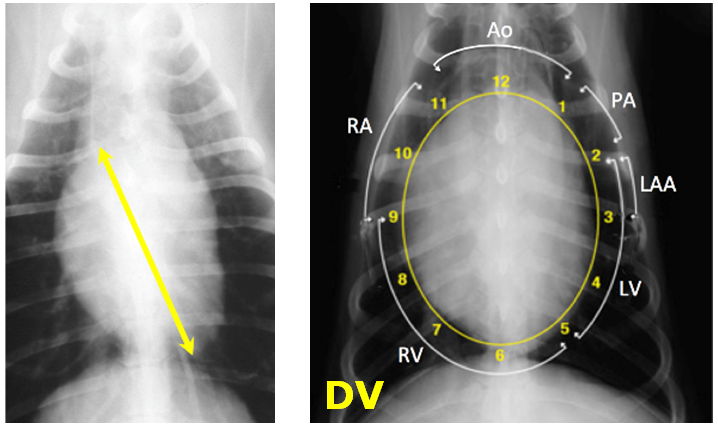

What is the normal size of feline heart in radiographic appearance?

Normal width (DV)

Normal short axis (lateral)

Normal long axis (lateral)

Normal heart – roughly ovoid, in middle of thorax

Hows is dogs heart like a clock face?

Enlargement bulges in specific areas, can relate to individual structure of chamber enlargement in dogs – like a clock face.

In DV left side is slightly more flat

In DV right side is rounded

What is the normal size of a dogs heart?

–< 2/3 width of thorax

Normal width (lateral)

–2.5 – 3.5 intercostal spaces wide

Normal height (lateral – 5th rib)

–2/3 height of thorax